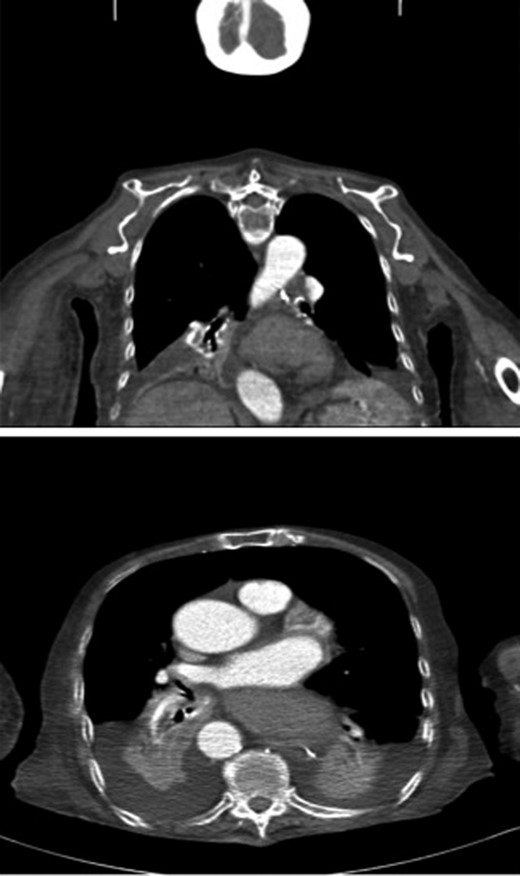

A 95-year-old Caucasian woman presented with worsening dysphagia, epigastric pain, retching without vomiting and hiccups over 5 months. Oesophagogastroduodenoscopy (OGD) was unsuccessful due to failed intubation. Fibreoptic nasoendoscopy revealed pooling of saliva in the piriform fossa and a diagnosis of pharyngeal pouch was initially made. Barium swallow was abandoned due to aspiration by the patient (Fig. 1).

Sequence of barium swallow examinations revealing upper oesophageal tightening and aspiration.